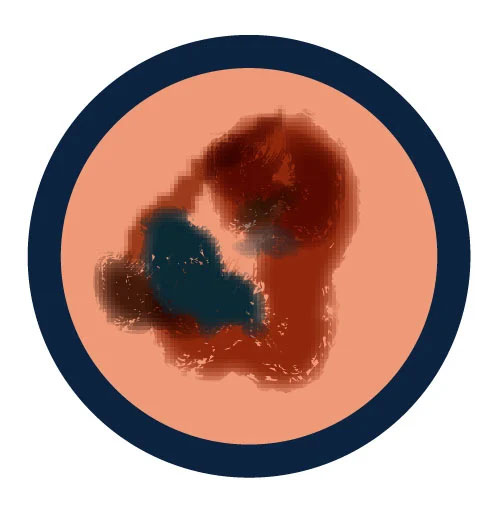

A is for Asymmetry

One half of a mole or spot does not match the other.

B is for Border

The edges of the spot are irregular, scalloped or poorly defined.

C is for Color

The color of the spot is not the same all over and may include different shades of brown or black, sometimes with patches of pink, red, white or blue.

E is for Evolving

The mole is changing in size, shape, or color.